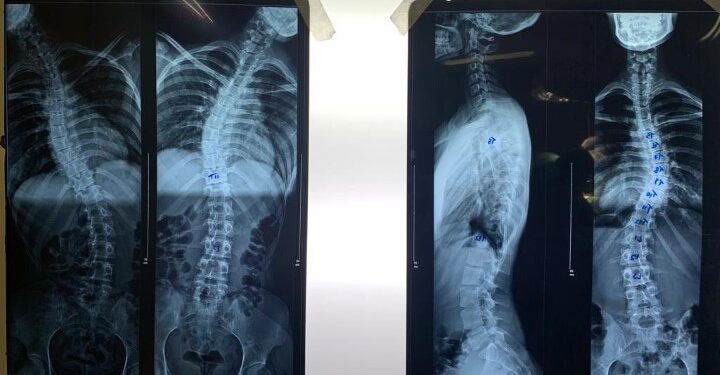

O Hospital Nossa Senhora das Dores (HNSD) realizou a primeira cirurgia para correção de escoliose idiopática com artrodese de Itabira. A paciente, uma mulher de 20 anos, passou por uma artrodese, que é uma fusão no local que apresentava as deformidades, onde foi colocado parafusos e hastes para manter a coluna o mais ereta possível. A cirurgia foi feita na última sexta-feira (7) e, segundo o médico responsável pelo procedimento, o ortopedista Glauber Henrique Costa Ferreira, “foi um grande sucesso”.

Ao todo, foram quatro horas de cirurgia, que contou com monitorização antes, durante e após o procedimento, com o objetivo de minimizar os riscos de lesão dos nervos e da medula. Ao final, devido ao protocolo para este tipo de cirurgia, considerada de grande porte, a paciente foi encaminhada para Unidade de Tratamento Intensivo (UTI), onde permaneceu por apenas um dia, sendo transferida na sequência para um apartamento. No último domingo (9), ela recebeu alta e conseguiu andar, o que atesta o sucesso de todo o tratamento.